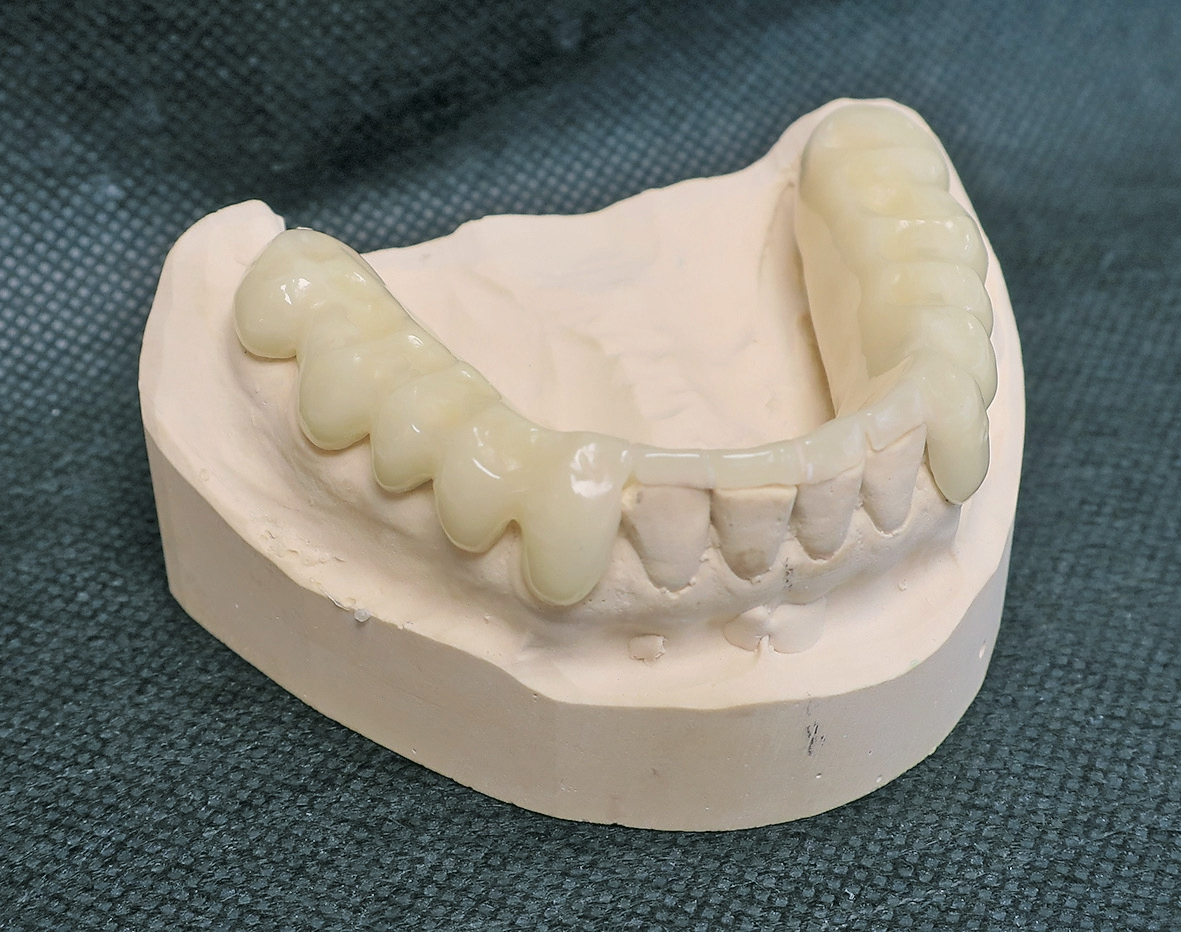

Eine therapeutisch erfolgreiche Position in dem dynamischen stomatognathen System ist identisch mit einem Element aus der Menge der physiologischen Positionen (Abb. 14). Die okklusalen Verhältnisse zahntechnischer Konstruktionen haben dem Reichtum an physiologischen Relationen und der Dynamik des Systems im Sinne einer Spielpassung zu entsprechen.